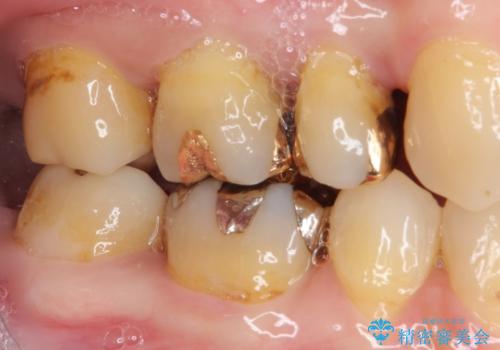

- 奥歯の裏側がしみるとのことで来院された患者様です。

矯正治療による歯肉退縮がおき、歯根にまで虫歯が波及していました。

虫歯が大きかったため、フルジルコニアクラウンにて補綴することとしました。

一部歯肉の中にまで虫歯が波及しており、汚れが溜まりやすくなっていましたが、クラウン装着後は汚れが溜まることはなくなりました。